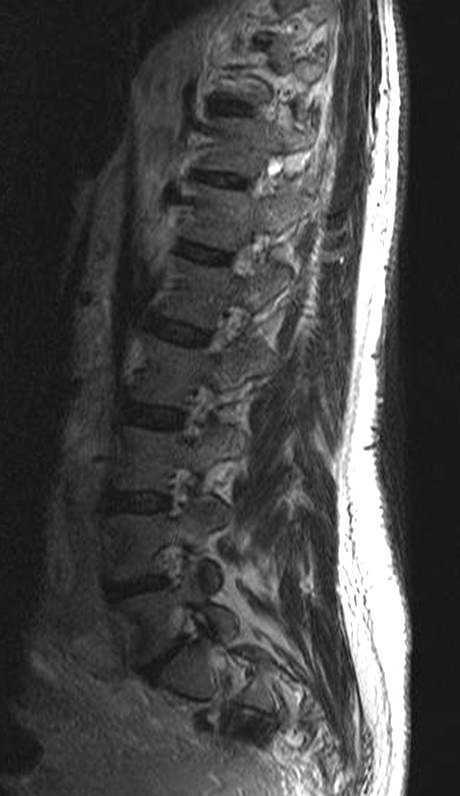

Se realizó una resonancia magnética (RM) de la columna lumbar (sin y tras contraste intravenoso) y se observaron, además de la masa retroperitoneal que comprimía la VCI, unas imágenes puntiformes y lineales hipointensas en todas las secuencias que ocupaban el espacio epidural adyacente al muro posterior de las vértebras lumbosacras, que se extendían a través de los agujeros de conjunción hacia las partes blandas perivertebrales (figs. 1-3). Esta alteración correspondía a estructuras vasculares dilatadas dependientes del plexo venoso epidural vertebral.

Fig. 1. Resonancia magnética ponderada en T1 (A) sagital línea media, (B) parasagital y (C) axial. (A) Aumento de la grasa epidural que comprime el saco tecal debido a lipomatosis (flecha); (B) imágenes hipointensas puntiformes en el espacio epidural anterior que corresponden a estructuras vasculares dilatadas del plexo lumbosacro (flechas); (C) masa retroperitoneal que engloba grandes vasos (asterisco). Se objetiva la presencia de lipomatosis (flecha blanca) y las estructuras vasculares dilatadas (punta de flecha blanca).